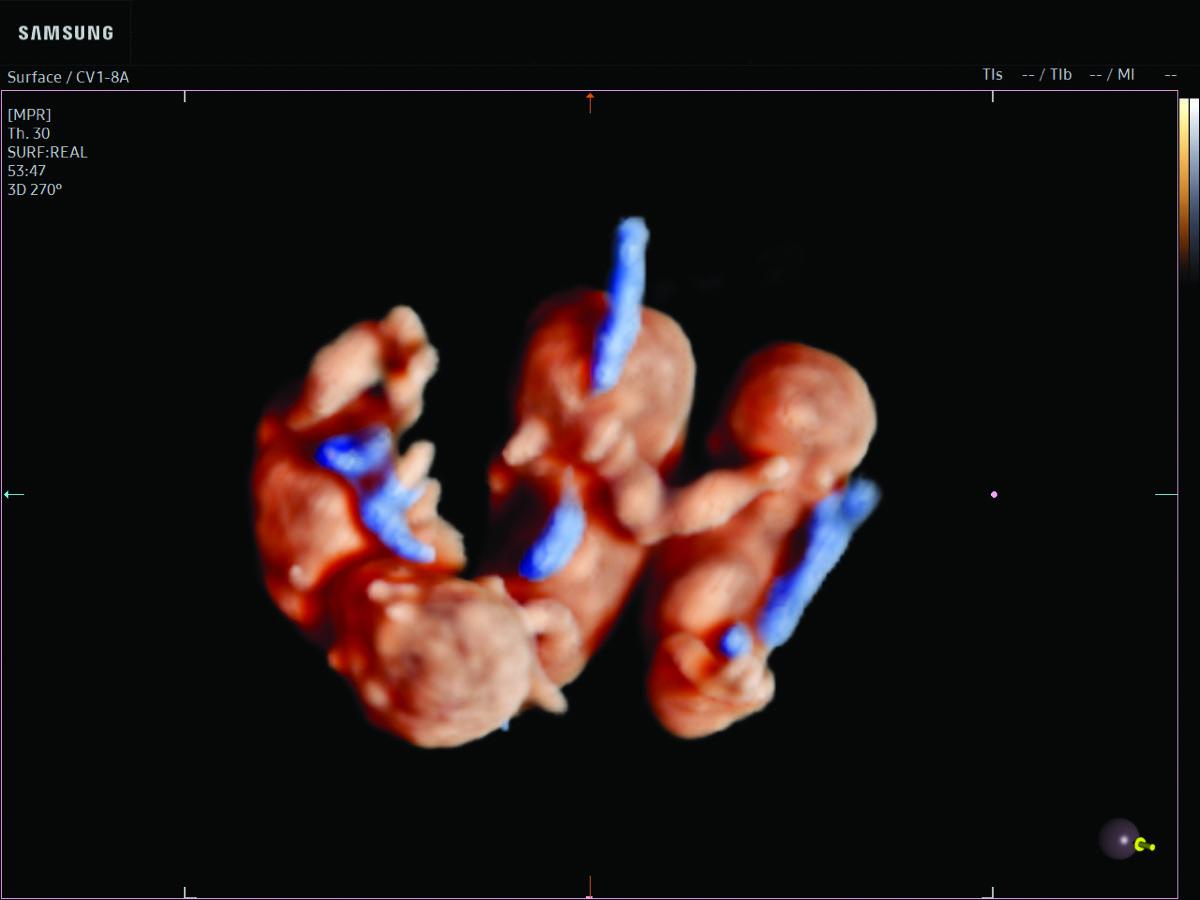

Comprehensive, advanced and expert MFM care for high-risk pregnancies

- Multiple births

- Fetal anomalies